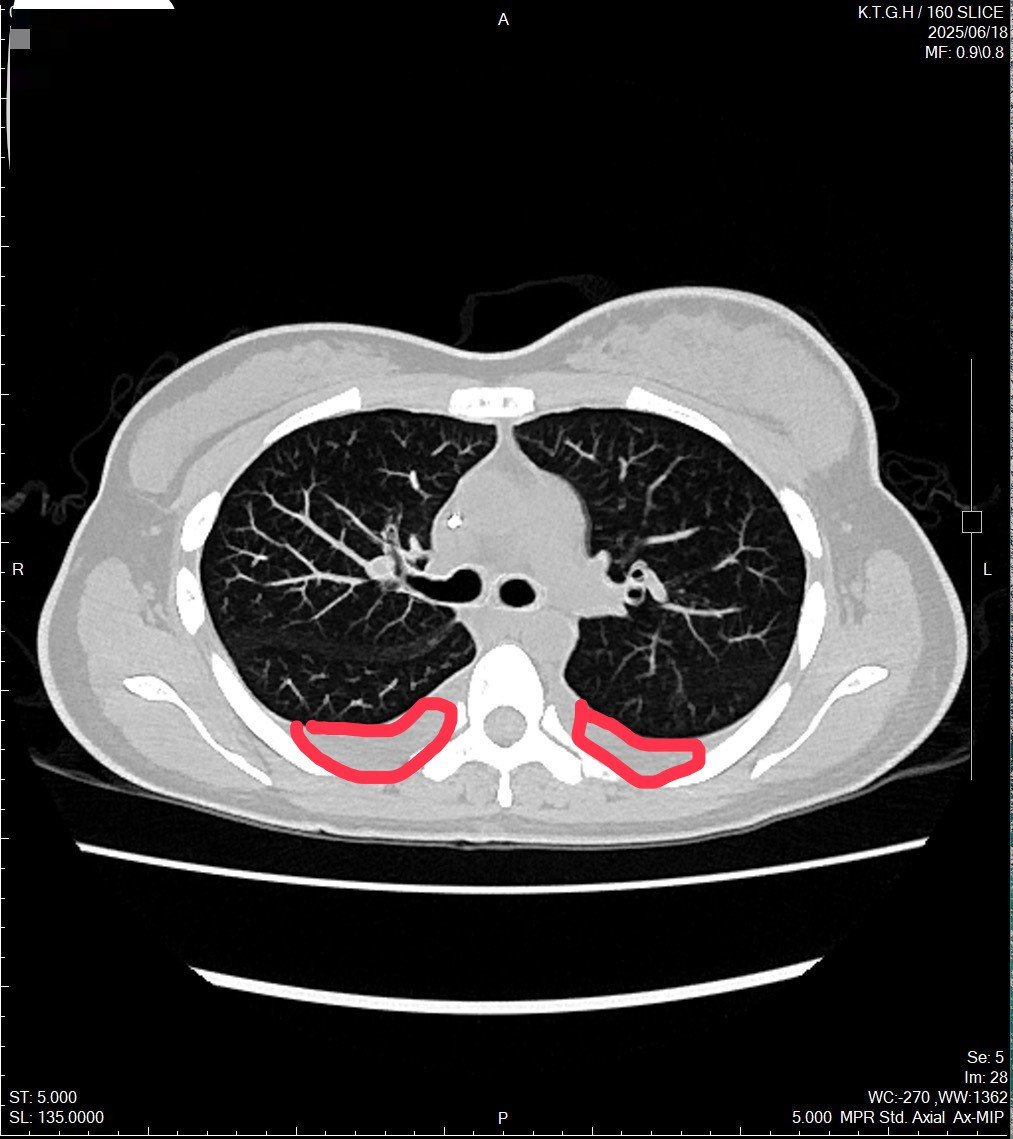

林小姐確診時,已罹患乳癌第四期,且癌細胞已轉移至骨骼與肺部,甚至造成雙側肺積水。

光田綜合醫院乳房外科廖志斌醫師指出,林小姐罹患的是最常見的「管腔型乳癌」,因此,醫療團隊評估屬於內臟轉移急症,先給於化學治療,之後再採用口服標靶合併荷爾蒙藥物治療。經過一段時間,林小姐的症狀逐漸獲得控制,生活品質明顯改善。